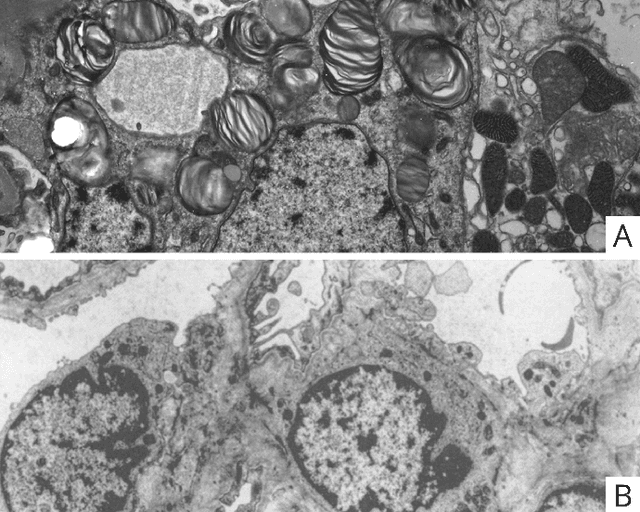

Abstract:Computational pathology is a field that has complemented various subspecialties of diagnostic pathology over the last few years. In this article a brief analyzis the different applications in nephrology is developed. To begin, an overview of the different forms of image production is provided. To continue, the most frequent applications of computer vision models, the salient features of the different clinical applications, and the data protection considerations encountered are described. To finish the development, I delve into the interpretability of these applications, expanding in depth on the three dimensions of this area.